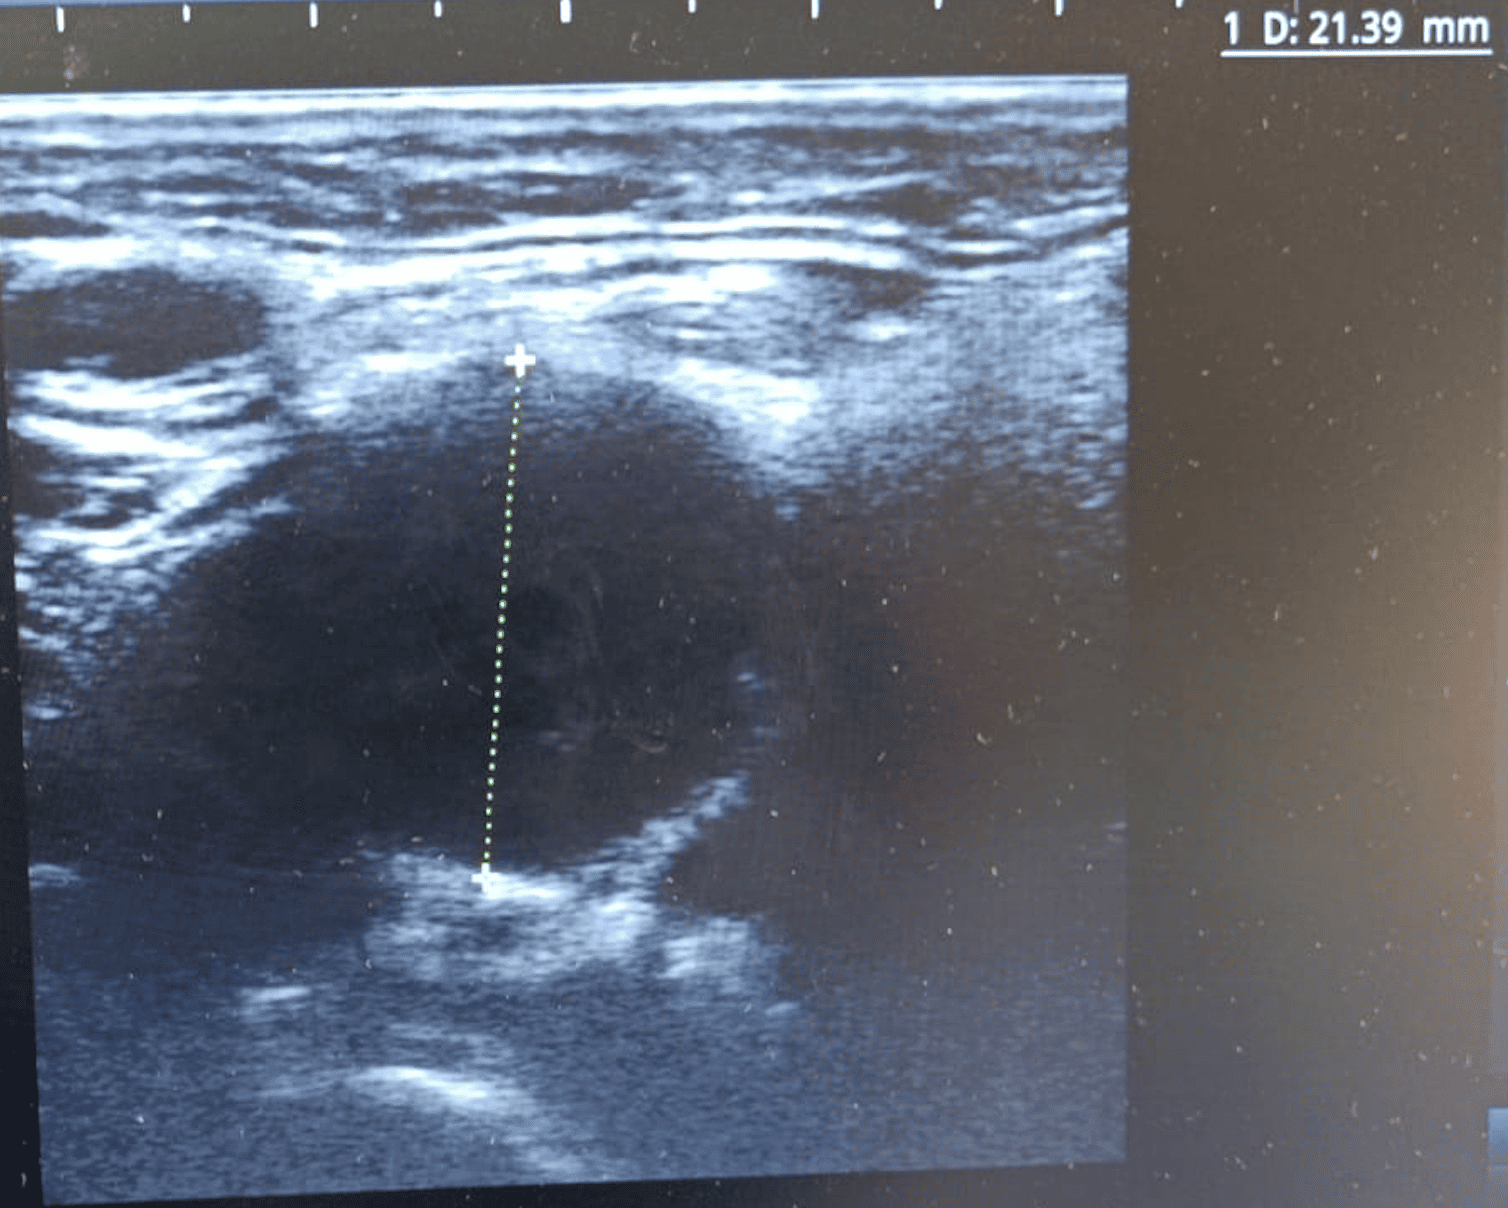

Hallazgos ecográficos

Ecografía cervical que muestra adenopatías hipoecoicas sólidas. En lado izquierdo, imagen de 24x32 mm con vascularización periférica en Doppler; en lado derecho, adenopatía de 20x18 mm con características similares. Hallazgos sugestivos de posible etiología maligna.